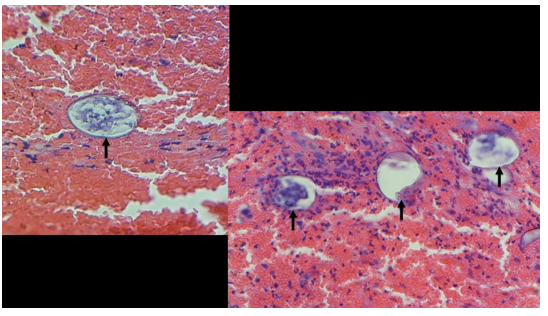

Figure 3: shows multiple parasitic ova embedded within a background of red blood cells and areas of necrosis and fibrosis.

Figure 4: shows high-power views of Schistosoma eggs found in different parts of the specimen, surrounded by red blood cells and infiltrates. The egg is seen to be oval-shaped, with no visible terminal or lateral spine on its shell. This appearance is consistent with Schistosoma japonicum species, the only Schistosoma species found in the Philippines.